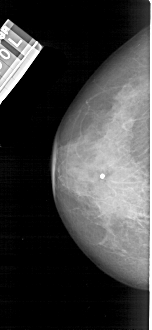

A_1683_1.LEFT_CC

LEFT_CC LINES 4936 PIXELS_PER_LINE 2266 BITS_PER_PIXEL 12 RESOLUTION 43.5 NON_OVERLAY